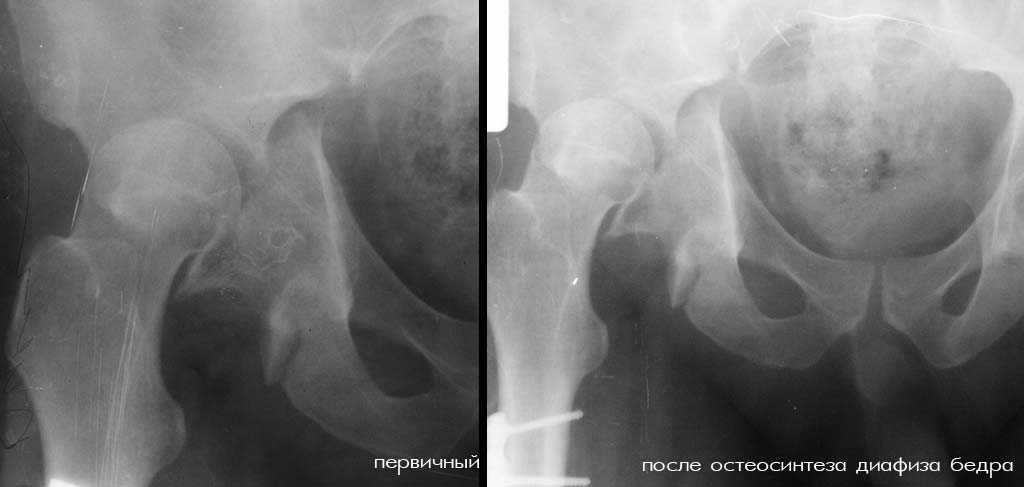

К нам переведен больной 36 лет (175 см рост, 105 кг масса тела), который 64 дня назад в ДТП получил множественную скелетную травму: перелом вертлужной впадины справа с задним вывихом бедра и повреждением крестцово-подвздошного сочленения справа, оскольчатым (тип C3) переломом диафиза правого бедра на границе с/3 - н/3, открытый (тип III В по Каплану-Марковой) краевой перелом мыщелков правой большеберцовой кости, закрытый поперечный перелом диафизов костей правой голени на границе с/3-н/3 (т.е. все повреждения справа). Судя по анамнезу, имело место сдавление правой голени и бедра около 1,5 часов. В ЦРБ (по месту получения травмы) был доставлен в тяжёлом травматическом шоке, отмечались признаки ОПН (в частности, олигурия и подъём уровня креатинина выше 300 ммоль/л). Судя по анамнезу, более месяца сохранялся резко выраженный отёк правого бедра. Из выписки известно, что безуспешные попытки закрытой репозиции вывиха бедра были выполнены при поступлении в ЦРБ. Больному также выполнен накостный остеосинтез диафиза правого бедра. Рана зажила первичным натяжением. Голень фиксирована гипсовой повязкой. В области правого коленного сустава остаётся обширная рваная рана с дефектом кожи (до 20x20 см), частично закрытая дерматомными лоскутами, из которой высевается полирезистентный acinetobacter. Продолжает эпизодически лихорадить (до 38), сохраняется лейкоцитоз (11-14 тыс), в ряде анализов крови отмечался сдвиг до миелоцитов (1-6%). В остальном - без видимой патологии. Отёк бедра в настоящее время незначительный. После перевода наложено вытяжение за бедро 12 кг. Хотелось бы узнать мнения о вариантах тактики лечения перелома вертлужной впадины и вывиха бедра (учитывающие и давность травмы, и сопутствующие повреждения). Хотя этот нюанс совсем немедицинский, но замечу, что больной не настроен на любые виды платной медицинской помощи. Имеющиеся рентгенограммы и КТ приложены. С уважением Игорь

Для более информативной оценки повреждений желательно сделать обзорный снимок таза и inlet, а для вертлужной впадины - проекции Judet. И конечно КТ, если возможно.

Я за агрессивную тактику- молодой пациент с поперечным трансвертлужным переломом таза,перелом задней стенки впадины с вывихом бедра+наружная ротация проксимального отломка таза с повреждением lig.sacroiliac interosseous anterior.Конечность в наружной ротации,как нерв?

Учитывая перелом задней стенки верл.впадины из доступа Кохера-Лангенбека репозиция-фиксация таза-вправление вывиха-синтез впадины.Фиксация таза на уровне передней и задней колонн во избежании ротационных смещений.Удаление пластины и реостеосинтез бл.штифтом-согласен.

Скорее всего перелом Т-образный и головка вроде бы цела. Я бы разобрал впадину и собрал обратно с фиксацией трансфрактурными винтами передней колонны и мостовидной пластинкой задней. Перед открытой реконструкцией возможно наложил бы аппарат таз бедро для низведения головки, если пластина на бедре выглядит надежной.

Считаю целесообразным провести реконструкцию вертлужной впадины после закрытия кожного дефекта. Срок 3 месяца не является критичным. Из моей практики, мы восстанавливали впадину через 8 месяцев.Больного наблюдаем в течении 2 лет ходит с полной нагрузкой,с легкой хромотой и незначительным болевым синдромом от эндопротезирования отказывается.Реконструкцию считаю провести из 2 доступов внутритазового и заднего или из расширенного внутритазового доступа. Операционная кровопотеря в таких случаях по нашей практике составляет 2-2,5 литров и не является критичной. Последующее эндопротезирование (по нашей практике) не требует удаления всех металлоконструкций и позволяет установить обычную бесцементную чашку.